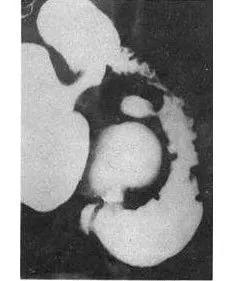

十二指肠球部溃疡,正位片龛影及黏膜纠集